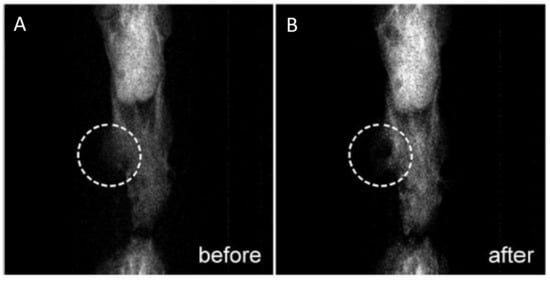

- Mehrmohammadi, M.; Shin, T.-H.; Qu, M.; Kruizinga, P.; Truby, R.L.; Lee, J.-H.; Cheon, J.; Emelianov, S.Y. In vivo pulsed magneto-motive ultrasound imaging using high-performance magnetoactive contrast nanoagents. Nanoscale 2013, 5, 11179–11186. [Google Scholar] [CrossRef] [Green Version]